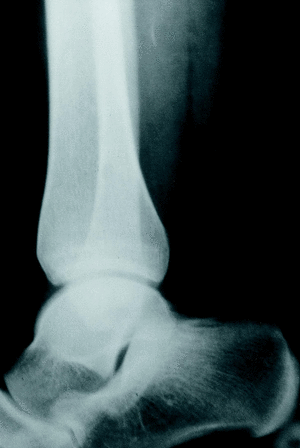

Desde 1990, se han identificado en el Servicio de Cirugía Ortopédica y Traumatología del Hospital USP-Santa Teresa de La Coruña 10 casos de músculos sóleos accesorios en 7 pacientes (tres casos bilaterales). Se trataba de 4 hombres y 3 mujeres, con una media de edad de 25 años (mínima: 4 y máxima: 42 años). En 6 casos, los pacientes acudieron a la consulta por presentar dolor en la zona aquílea durante el ejercicio físico, identificándose otros 2 casos al examinar el lado contralateral y un caso bilateral (el niño de 4 años) acudió a consulta porque sus padres estaban inquietos entre el aspecto de las regiones retromaleolares tibiales. En la exploración física se apreciaba en todos los casos, una tumoración retromaleolar interna del tobillo (fig. 1), ocasionalmente sensible a la palpación y que provocaba molestias con los ejercicios de estiramiento selectivo del sóleo en aquellos casos previamente sintomáticos; el tendón de Aquiles aparecía de grosor normal y sin nódulos en su interior en todos los casos. En los casos en que se realizó un estudio radiográfico, se podía apreciar una obliteración del triángulo de Käger (grasa preaquílea) por una masa de partes blandas (fig. 2). En todos los casos, se realizó un estudio ecográfico en el que se confirmó la existencia de una masa preaquílea, bien delimitada, con una ecogenicidad similar a la del músculo estriado, que finalizaba a una distancia variable del calcáneo dependiendo de su tamaño (fig. 3). En los 2 primeros casos, se realizó además un estudio de RM para confirmar el diagnóstico de músculo sóleo accesorio (fig. 4). Tras el diagnóstico, se instauró un régimen de estiramiento selectivo del sóleo y reducción del nivel de actividad física hasta la desaparición de la sintomatología, seguida de la reincorporación progresiva a la actividad previa por debajo del nivel de molestia, hasta la normalización de los pacientes. En todos los casos menos uno (el paciente de más edad) fue posible retomar la actividad física sin limitaciones; en éste último caso, el paciente se encuentra subjetivamente mejor, aunque persiste el dolor al correr más de 15 a 20 minutos, por lo que se encuentra a la espera de decidirse a realizar una fasciotomía del sóleo accesorio.

Figura 2. Radiografía lateral del tobillo de un paciente portador de un músculo sóleo accesorio, en el que se aprecia la obliteración de la grasa preaquílea por una masa de partes blandas de contorno redondeado, correspondiente a un músculo sóleo accesorio.